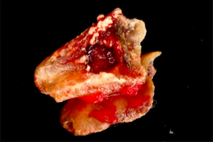

- Surgical removal of excessive gum tissues and extraction of multiple poor prognosis teeth were carried out as well